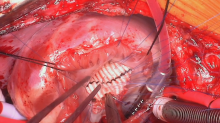

The baffle was secured with running 6-0 polypropylene suture and further supported with multiple interrupted 6-0 sutures reinforced with bovine pericardial pledgets placed in a horizontal mattress fashion. The aortic and tricuspid valves were tested and deemed competent. The RVOT was evaluated with an appropriately sized dilator and found to be adequate.